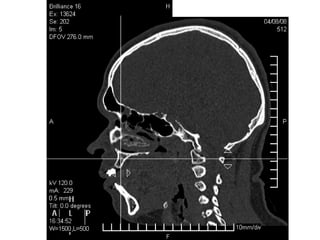

Tomografía computarizada

De seno maxilar corte sagital.

Area de implantación

Dentaria.

Material osteoconductor

para elevar el piso antral

Nuevo piso del seno y su

margen de seguridad para

contener el implante

Tomografía computarizada De senomaxilar corte sagital. Area de implantación Dentaria.